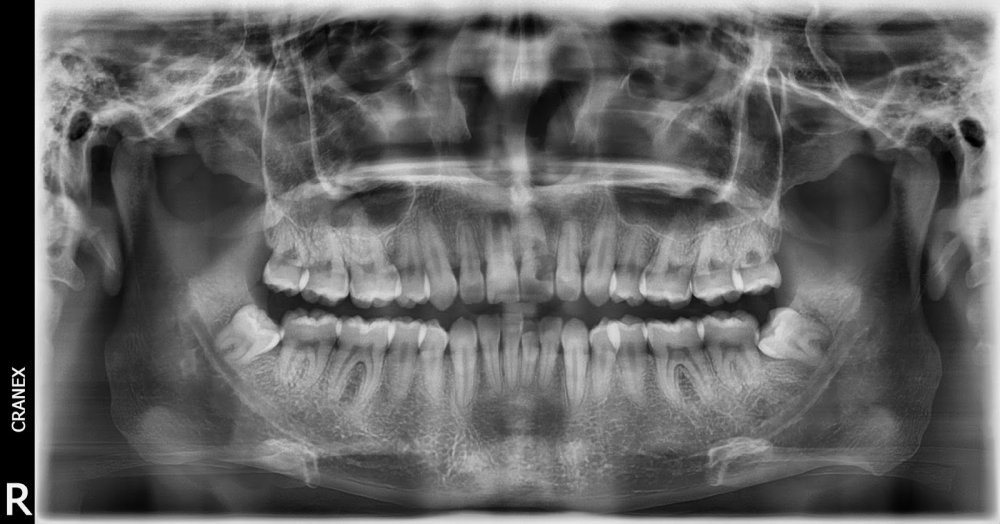

Caso Radiográfico N° 02: Seudo-infantilismo pulpar y resorción radicular externa asociado a antecedente traumático

Paciente de 20 años de edad de sexo masculino, que acude a nuestra institución para descartar caries con compromiso pulpar en pieza 2.1.

A la evaluación de la radiografía panorámica, observamos que la pieza 1.1 presenta desarrollo radicular incompleto caracterizado por cámara pulpar, conducto radicular y foramen apical amplios, compatible con seudo-infantilismo pulpar. Proceso osteolítico periapical de límites definidos compatible con granuloma periapical.

“El cuadro radiológico particular denominado seudo-infantilismo pulpar es propio de adolescentes. Se presenta casi exclusivamente en los dientes antero-superiores y es de origen traumático. Sus características radiográficas son las siguientes: La imagen de un diente permanente que ha hecho erupción y que presenta un desarrollo radicular incompleto; su cámara, su conducto y su foramen aparecen considerablemente amplios, como corresponde a un diente en vías de desarrollo”, contrastando con la formación completa o casi completa de los demás dientes permanentes. 1.